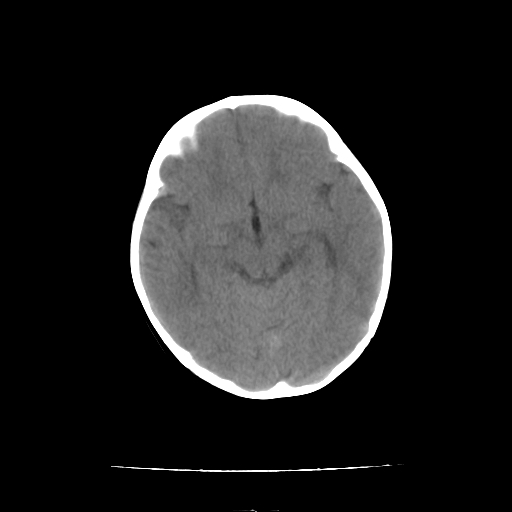

女,10个月,头外伤三天,伤后爱哭闹,吃奶少,睡觉不踏实。

左侧颞极蛛网膜囊肿

1)左侧颞极蛛网膜囊肿。2)第四脑室出血?

1、左侧颞极蛛网膜囊肿;2、第四脑室出血?3、右侧顶叶脑裂畸形伴灰质异位?